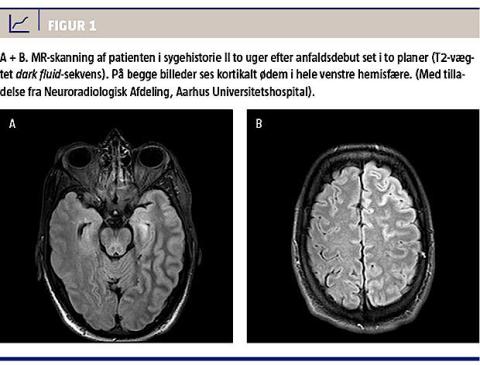

Patienten blev genindlagt, da han var 44 år, med bevidsthedssvækkelse, afasi og hemiparese, igen højfebril og med enkelte krampeanfald. MR-skanninger af cerebrum viste normale forhold ved indlæggelsen, men viste efterfølgende kortikalt ødem i hele venstre hemisfære (Figur 1). Han måtte igen overflyttes til en neurohabiliteringsafdeling. Han havde ikke haft migrænesymptomer imellem disse tilfælde.